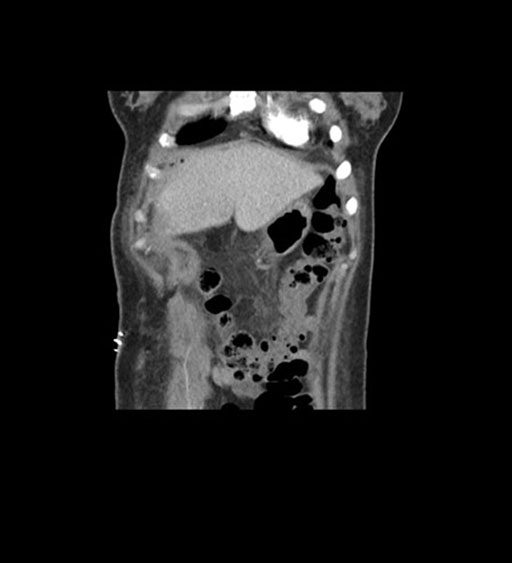

Coronal Arterial

Coronal Venous

Imaging analysis

Based on initial findings, which issue(s) would you be most concerned about?